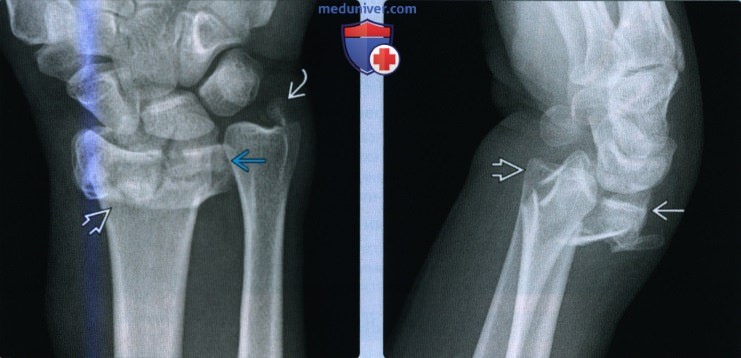

(Слева) На заднепередней рентгенограмме выявляется оскольчатый перелом лучевой кости в типичном месте с укорочением более 5 мм, что вызывает натяжение треугольного фиброзно-хрящевого комплекса. Отрывной перелом основания шиловидного отростка локтевой кости способствует нестабильности дистального лучелоктевого сустава из-за разрыва треугольного фиброзно-хрящевого локтевого якоря.

(Справа) На боковой рентгенограмме у этого пациента определяется тыльное угловое отклонение дистального эпиметафиза лучевой кости более 20°. Обратите внимание на ладонный вывих головки локтевой кости. Восстановление анатомического положения дистального эпиметафиза лучевой кости важно для восстановления целостности дистального лучелоктевого сустава. (Слева) На рисунке показаны повреждения, способствующие нестабильности дистального лучелоктевого сустава, включая сложные переломы дистального эпиметафиза лучевой и локтевой кости. Отломки лучевой кости вдавлены и отклонены под углом. Треугольный фиброзно-хрящевой комплекс разрывается при отрыве шиловидного отростка с фиброзно-хрящевым комплексом от локтевой кости и разрыве локтезапястных связок.